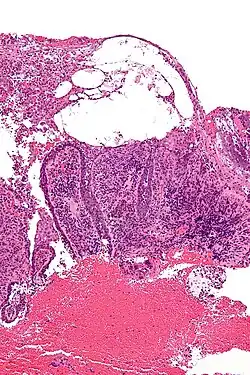

Micrograph of pemphigus vulgaris with the characteristic "tombstoning". H&E stain.

Pemphigus is an autoimmune disease caused by antibodies directed against both desmoglein 1 and desmoglein 3 present in desmosomes. Loss of desmosomes results in loss of cohesion between keratinocytes in the epidermis, and a disruption of the barrier function served by intact skin. The process is classified as a type II hypersensitivity reaction (in which antibodies bind to antigens on the body's own tissues). On histology, the basal keratinocytes are usually still attached to the basement membrane leading to a characteristic appearance called "tombstoning". Transudative fluid accumulates in between the keratinocytes and the basal layer (suprabasal split), forming a blister that is easily dislodged when a lateral force is applied, resulting in what is known as a positive Nikolsky's sign.[6] This is a contrasting feature from bullous pemphigoid, which is thought to be due to anti-hemidesmosome antibodies, and where the detachment occurs between the epidermis and dermis (subepidermal bullae). Clinically, pemphigus vulgaris is characterized by extensive flaccid blisters and mucocutaneous erosions. The severity of the disease, as well as the mucosal lesions, is believed to be directly proportional to the levels of desmoglein 3. Milder forms of pemphigus (like foliacious and erythematoses) are more anti-desmoglein 1 heavy.